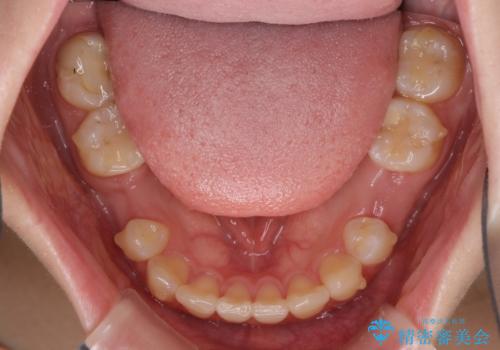

欠損と残存乳歯 矯正治療とインプラント治療

- 残存した乳歯や歯の欠損、歯並びを気にして来院された患者様です。

乳歯を残した状態は予後がよくないこと、矯正治療と補綴治療を総合的に進めていきたいとのことで、インビザラインによる矯正治療とインプラント補綴治療を並行して進めていくこととしました。